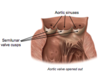

What are the contents of the middle mediastinum?

The pericardial sac and heart

The origins of the: aorta, Superior vena cava, pulmonary trunk

The phrenic nerve- splits into L and R phrenic nerves, runs in the middle mediastinum to reach the diaphragm.

What part of the heart attaches to the central diaphragmatic tendon?

The fibrous pericardium attaches to the central diaphragmatic tendon, meaning if the diaphragm moves the thoracic contents also move.